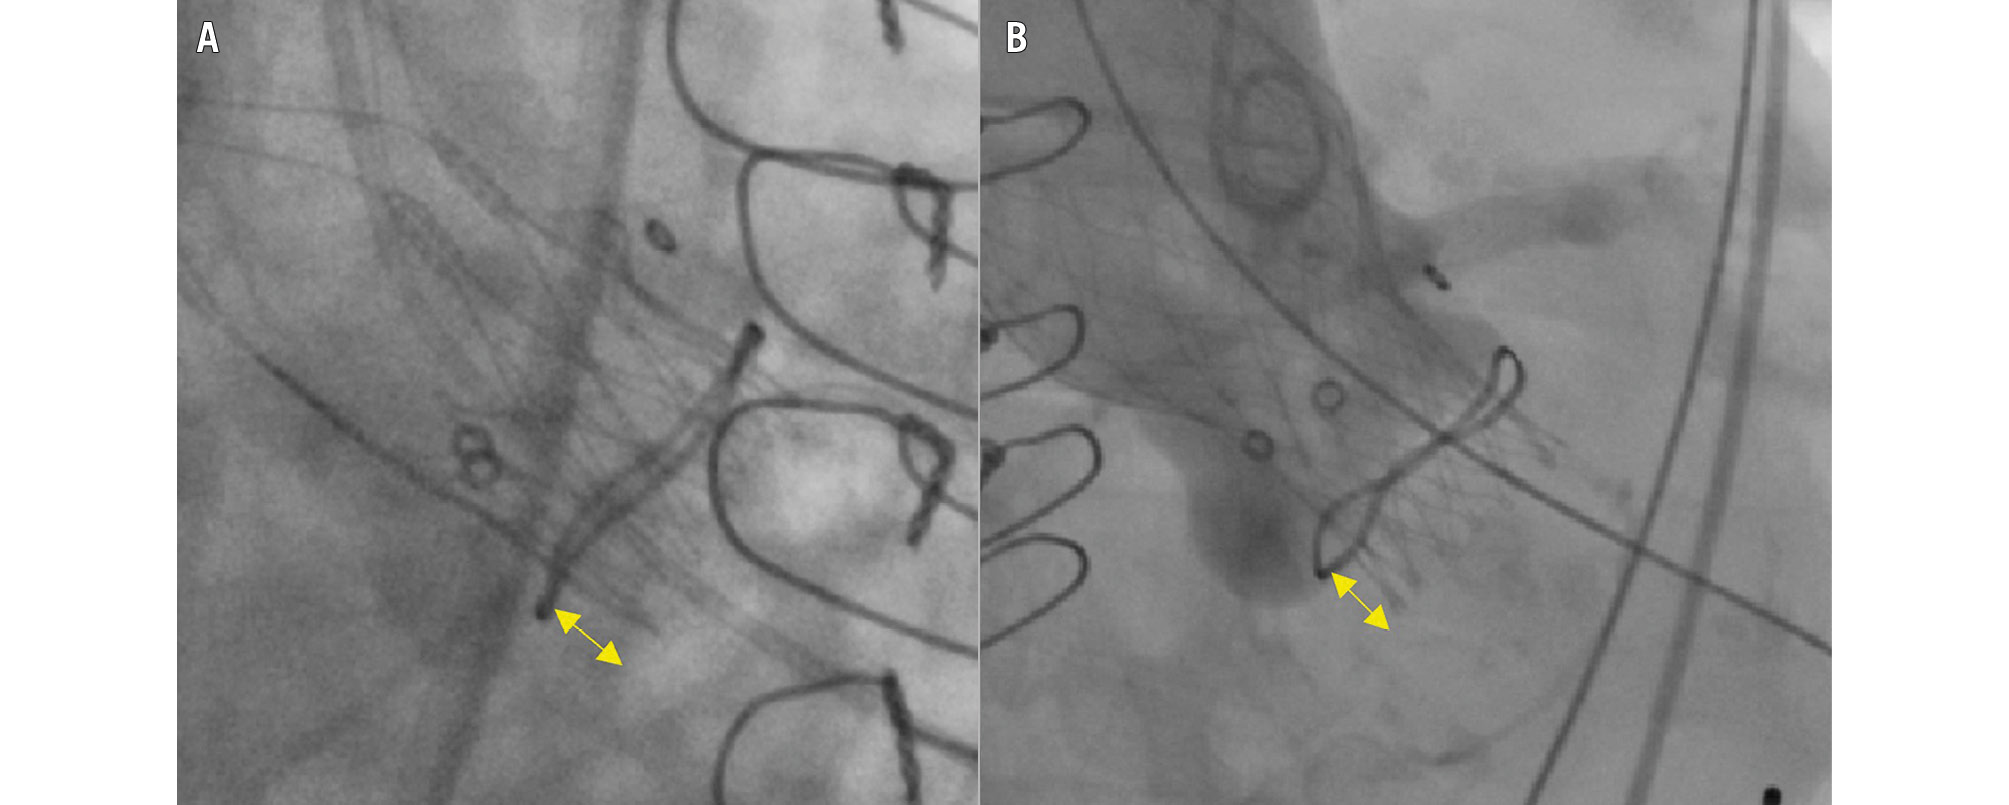

The implantation depth of the prosthesis was determined upon final angiography at the site of the former non-coronary cusp and defined as the distance between the ventricular aspect of the bioprosthetic ring and the inflow segment of the THV (Figure 1). Malpositioning was defined as incorrect positioning of the device (too high: implantation depth <0 mm; too low: implantation depth ≥10 mm) requiring intervention − including the implantation of a second valve or surgical valve replacement − or leading to valve dysfunction (aortic regurgitation [AR] ≥moderate or mean gradient ≥20 mmHg).

Figure 1. Implantation depth measurements. A) ACURATE and B) EVOLUT. The double-headed arrows denote the implantation depth at the non-coronary cusp. ACURATE: ACURATE neo/neo2 group; EVOLUT: Evolut R/PRO/PRO+ group